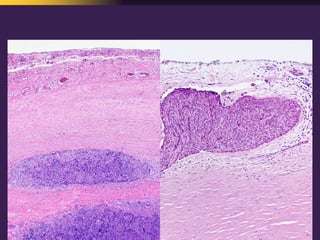

This document discusses mediastinal pathology using a compartmental approach. It describes the anatomy of the mediastinum and divides it into anterior, middle, and posterior compartments. Each compartment contains different structures and has a characteristic distribution of lesions. For example, 50% of lesions occur in the anterior compartment, which contains the thymus. The thymus is the most common site of lesions in the anterior compartment. Thymomas are the most common epithelial tumors of the thymus and mediastinum.